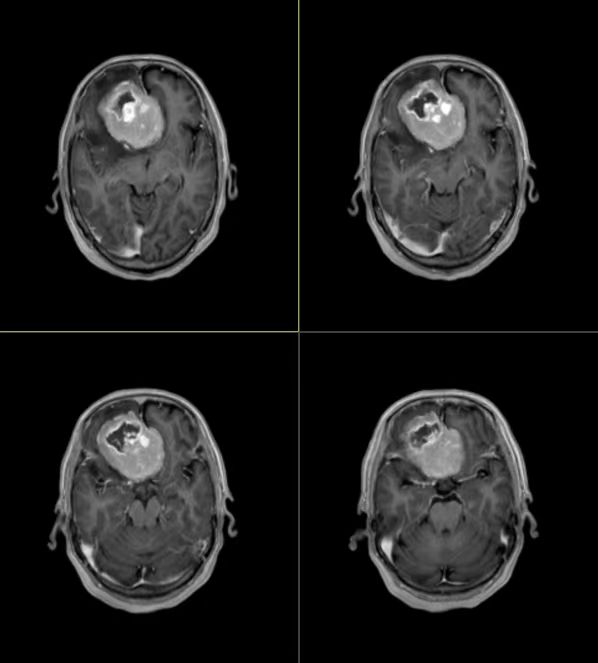

术前影像结果

就诊后,兰大二院副院长、神经外科主任医师潘亚文教授结合患者既往病史及检查检验结果,明确诊断为前颅底脑膜瘤,且右额叶水肿,大脑镰下疝形成。大脑镰下疝如果不及时进行治疗,会导致脑部组织受到压迫,出现颅内压增高的情况,严重时还会导致脑疝进一步加重,出现生命危险。关键时刻,兰大二院立即为患者开通绿色通道,同时潘亚文教授团队经过详细周密的术前讨论,于7月19日为患者实施了颅底肿瘤切除术。

手术由潘亚文教授主刀,副主任医师梁强协助。考虑到患者年迈,手术采用右侧“额外侧微创入路”的方式进行,术中可见肿瘤通体鲜红,质地韧,周边脑组织大片水肿将其包裹。术中,缓慢释放瘤周侧裂里的脑脊液,释放颅内压力,在狭小的操作空间里,阻断肿瘤大部分血供。“拔起萝卜带起土”,整块切除肿瘤必然省劲轻松,但势必会造成脑组织的牵拉损伤加剧,而这对83岁高龄的老人来说,往往难以承受。为了最大可能地挽救生命,降低损伤,潘亚文教授采用了费时费力但无牵拉无损伤的“分块切除”策略,他一边控制出血量,一边小心翼翼地取出肿瘤,直至瘤体切除干净。